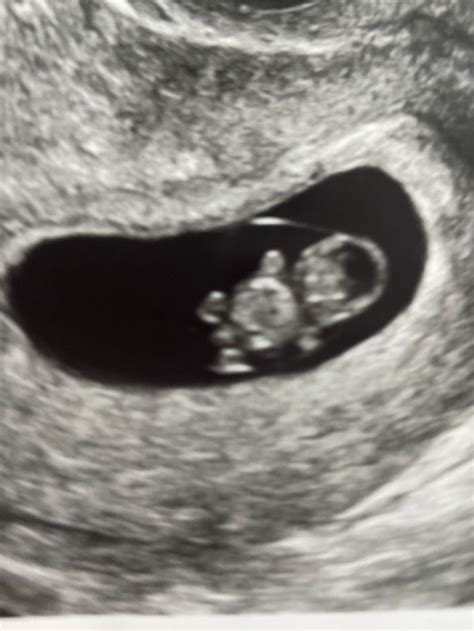

What Can Be Seen on an 8 Week Sonogram?

At 8 weeks, the fetus is still very small, but several key structures can be visualized:

• Gestational Sac: A fluid-filled structure that contains the developing embryo.

• Yolk Sac: A small, round structure that produces blood cells and helps in the early development of the embryo.

• Embryo: The developing fetus, which is about the size of a raspberry at this stage.

• Heartbeat: The fetal heartbeat is usually detectable and can be seen as a rapid flickering on the ultrasound screen.

• Neural Tube: The early stages of the brain and spinal cord can be observed.